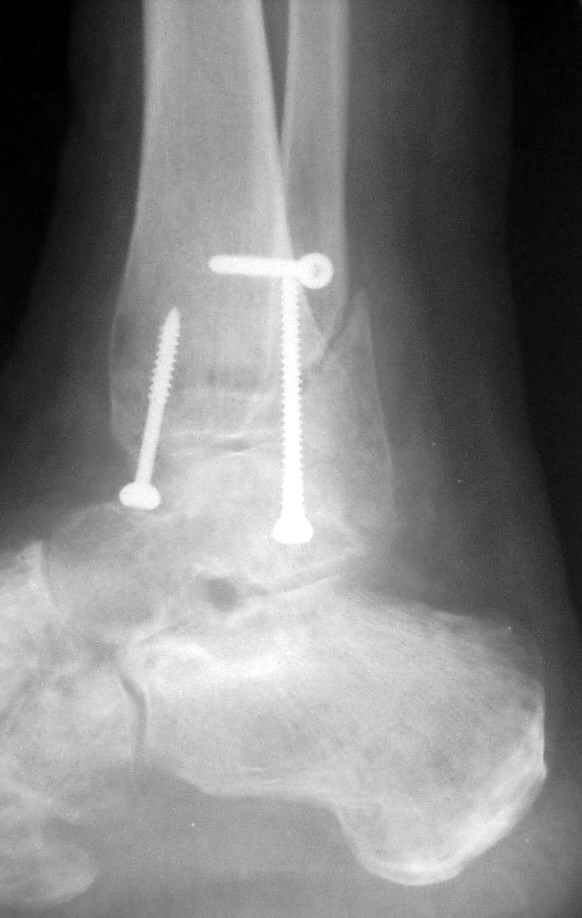

15 ноября прямой

15 ноября боковой

15 ноября трехчетвертной

Риторический вопрос - в каком руководстве рекомендован такой способ остеосинтеза наружной лодыжки?

Очевидно, такой результат операции был запрограммирован. При невосстановленной длине и практически нефиксированной малоберцовой кости (этот кортикальный винт - как карандаш в стакане), при неустраненном подвывихе, невправленной и тоже нефиксированной внутренней лодыжке нет стабильной вилки сустава. Если такую операцию сделать даже сразу, а не через 4 месяца, то результат ожидаем

тот же.

Вариант с артродезом уже обсудили. Хотя, после увиденых снимков, пессимизм насчет восстановительной операции у меня, например, несколько уменьшился. Особенного уж какого-то остеопороза не видно даже на январских снимках. Можно черед мини-доступы убрать винты, аппаратом вправить малоберцовую кость, устранить подвывих стопы. Ну а дальше фиксировать малоберцовую пластиной сзади. А может, и напряженной Y-спицей попробовать - Анатолий Федорович, как Вы полагаете? Внутреннюю - то, что осталось, если уже не получится сделать спицами и проволокой, то что-то типа пластики дельтовидной связки. А может, и не трогать ее вовсе... В общем, выбор непростой,

Если до сих ничего не сделано, с артродезом сустава в данный момент я бы повременил, на выставленных январских снимках хорошо сохранившийся сустав, а в "мортиз" (трехчетвертной) и на боковых снимках не менее 5 мм укорочение малоберцовой кости. Косые переломы лучше фиксировать пластинами, как то мы разбирали случай, где было отмечено, что это закон "таранная кость всегда следует за малоберцовой".